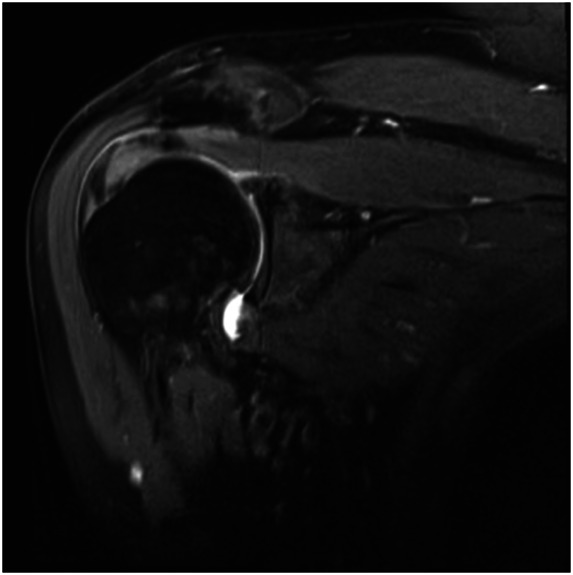

Augmentation Techniques for Rotator Cuff Repairs.

» Despite enhanced understanding of risk factors for failure and enhanced surgical repair techniques, the risk for failure of the rotator cuff to heal after surgery is still substantial.» A patient-specific approach to augmentation is essential, with decisions based on tear and patient characteristics.» Augmentation can improve repair strength and promote cellular infiltration, which collectively contribute to better healing outcomes.» Augmentation strategies may improve outcomes in rotator cuff repairs, particularly in high-risk cases; however, there is a lack of consensus among surgeons on the most effective strategies for each scenario.